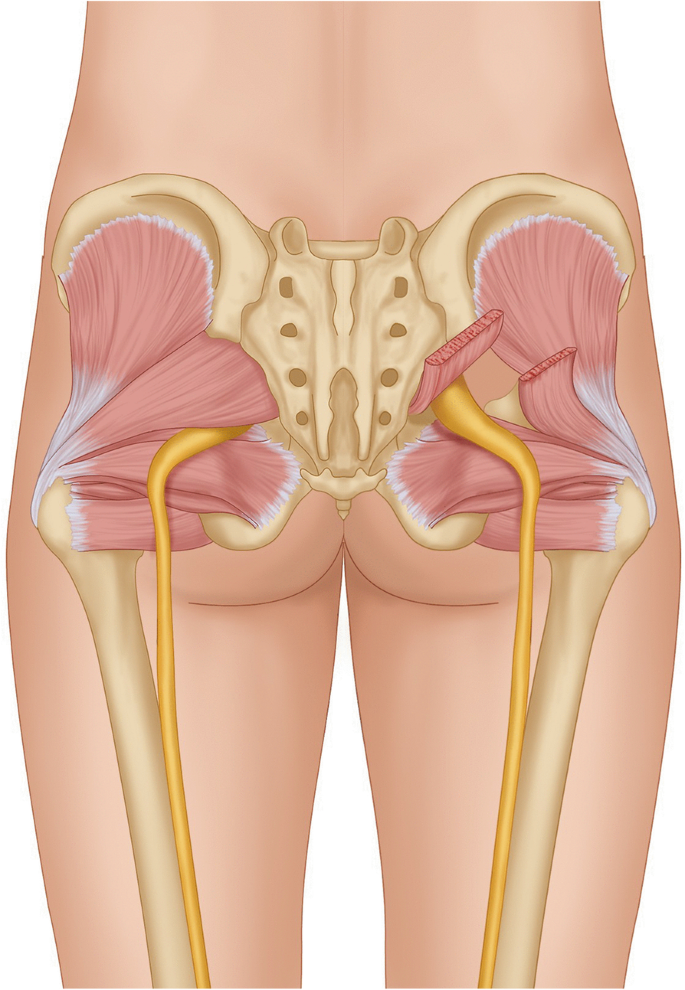

Анатомия мышц: Пириформис